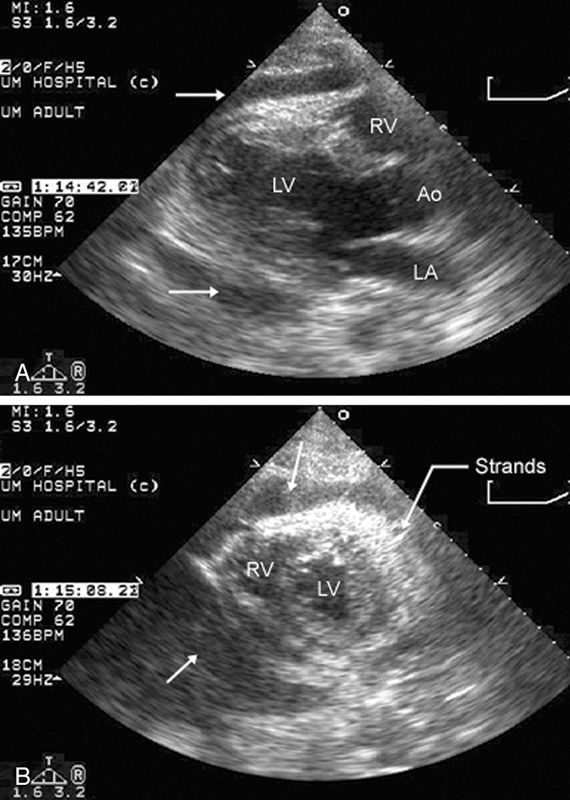

فحوصات تشخيصية لبعض امراض القلب والشرايين التاجية